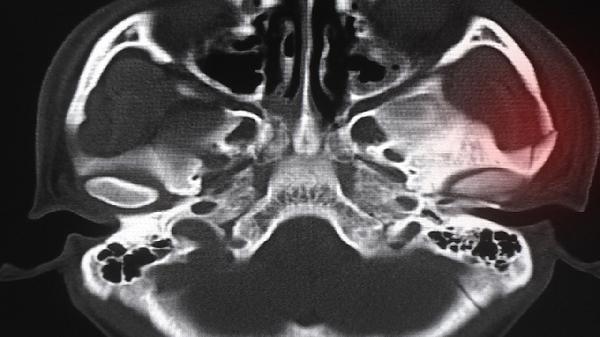

医学上判断骨骺线闭合的金标准是拍摄手腕部或膝关节X光片。当生长板完全钙化呈闭合状高密度影,且骨骼两端形成连续骨皮质时,表明骨骺线已闭合。该检查需由放射科医师结合骨龄图谱进行专业评估。

影像学显示长骨两端骨骺与干骺端之间的透亮带消失,代之以致密骨小梁连接。常见闭合顺序为远端指骨14-16岁→桡骨远端16-18岁→股骨近端18-20岁,个体差异受遗传和激素水平影响。

通过左手腕部X光片对比Greulich-Pyle骨龄图谱,若骨龄达到男性18岁、女性16岁标准,且骨骺线完全消失,则确认生长终止。但需注意约5%人群存在骨龄与实际年龄不符的情况。